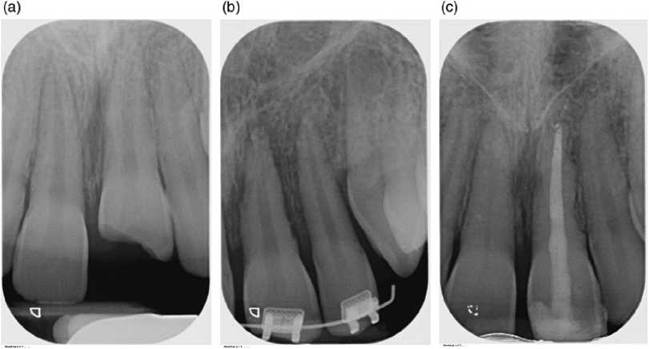

Resorption of the root apex as a result of orthodontic treatment, trauma or due to chronic AP can alter the shape and there- fore the appearance of the root apex [112]. Blunting of the root end is a typical feature of teeth that have undergone orthodontic tooth movement, while those affected by chronic AP may become flattened or adapt a ragged, uneven appearance. The root ends of teeth that have suffered traumatic injuries may develop any of the changes outlined above. Repair of root tips damaged by resorption can undergo repair with new cementum deposition, but features of the previous tooth destruction generally persist (Figure 6.3).

Figure 6.3 Dental trauma with external inflammatory resorption. (a) Periapical radiograph of maxillary central incisor teeth following a traumatic dental injury in which tooth 21 was severely intruded. (b) Within one week tooth 21 had undergone external inflammatory resorption with the development of excavations on the root surface of the tooth and associated radiolucencies in the adjacent bone. The entire root length, including the apical third, was involved. (c) Periapical radiograph of tooth 22 one year after the injury demonstrates resolution of the apical periodontitis and cessation of the resorptive process, although the shape of the root surface has been permanently altered.